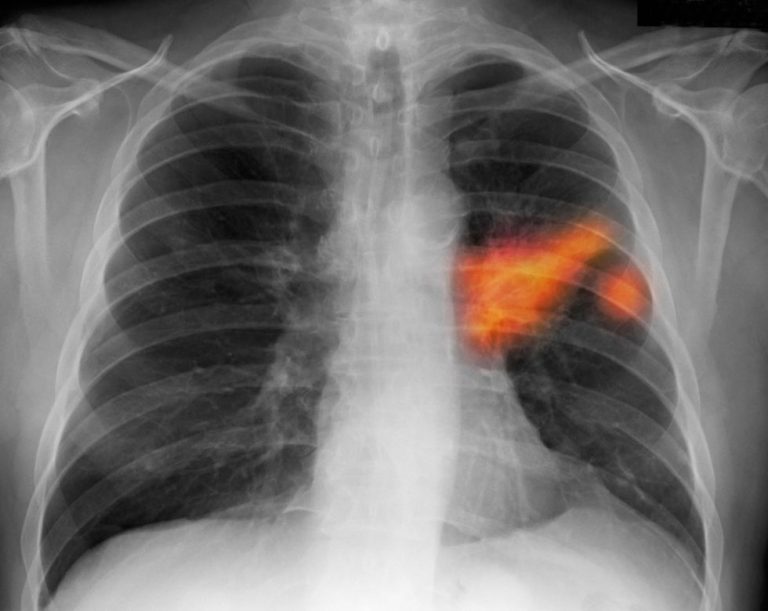

Cancro ai polmoni: un test delle urine per la diagnosi

Cancro ai polmoni: l’intelligenza artificiale rileva i primissimi segnali